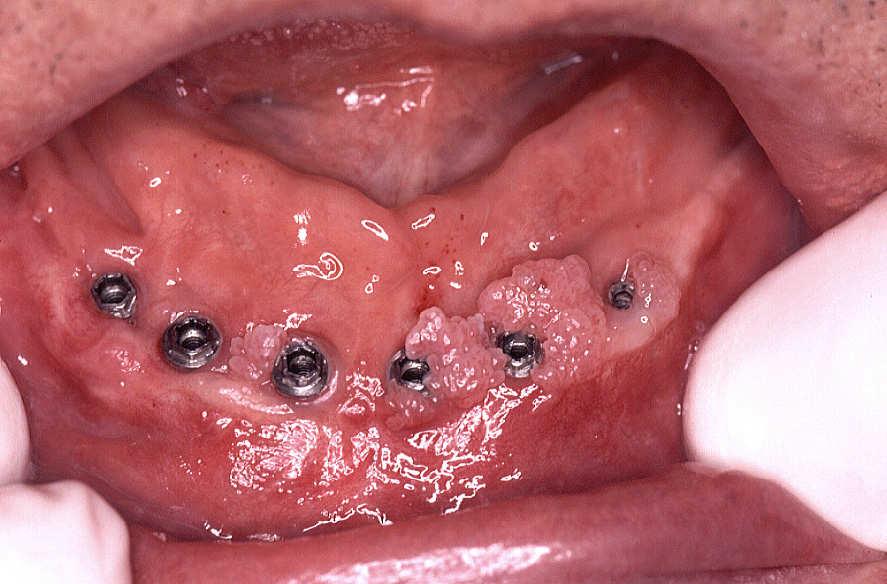

Patient, PCR positively for HPV categorizes. The papillomas are around of the titan implants, without prosthesis,

With help of a 810nm diodes lasers and a 400 micron fiber, 2.0 watts of performance with CW are removed all neoformation without locally Anestesie. There is sutures